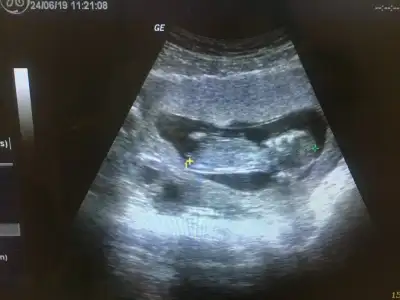

Kızlar merhaba🤗🤗 Ben de 14. Haftadayım cinsiyetini henüz öğrenmedim tabi merak ediyorum ilk hamileliğim 🤔🤔 İnternette bir yazıya denk geldim nub teorisine göre cinsiyet belirleme çoğunlukla doğru çıkıyormuş.Nub teorisi ultrasondaki minnoşların iki bacak arasındaki çıkıntı hafif dik ise erkek parelel ise kızmış 😂😂 tabi ben ultrason görüntüsünü evirdim çevirdim anlamadım pek internette örnekleri var bir bakabilirsiniz belki sizin minnoşların daha net görünür 🤗🤗

Yaa ne güzel Allah bağışlasın 🤗 Ben çözemedim henüz Çarşamba kontrolüm var ama söyler mi bilmem 🤔🤔 ultrason görüntüsü böyle belki siz anlarsınız ben anlayamadım 😌

Eklentiler

• 22B4EBF4-D731-4CFE-ACD2-6CB41755BB3F.webp

22B4EBF4-D731-4CFE-ACD2-6CB41755BB3F.webp

32,1 KB · Görüntüleme: 81